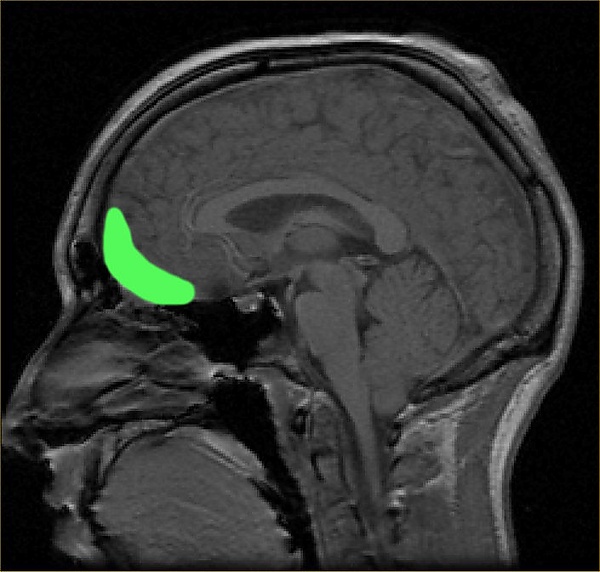

Орбитофронтальная кора

Орбитофронтальная кора (ОФК) — участок префронтальной коры в лобных долях головного мозга, принимающий участие в принятии решений. У человекообразных обезьян ОФК представлена совокупностью полей Бродмана под номерами 11, 12 и 13; у людей эта кора представлена полями 10, 11 и 47[1].

Орбитофронтальная кора анатомически синонимична вентромедиальной префронтальной коре. ОФК выделяется отдельно, поскольку содержит определенные нейронные связи, а также выполняет строго определенные функции. Принято считать, что ОФК является частью префронтальной коры, которая получает сигналы от магноклеточных нейронов, медиальных ядер таламуса, и принимает участие в представлении эмоций и поощрений во время принятия решений[2]. Название ОФК получила из-за своего расположения в области лобных долей, находящейся выше глазниц (орбит).